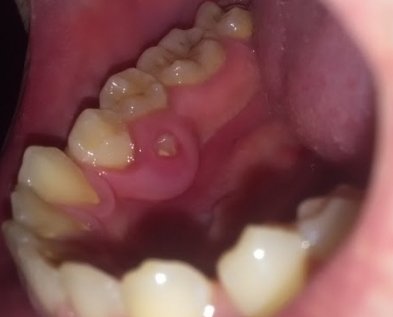

Семь лет назад лечил зуб, сделали хорошую пломбу, которая до сих пор держится, но на десне этой пломбы, два месяца назад, появился прыщик. Потом он превращался в шишку и со временем исчезал, и так много раз. Был сегодня у стоматолога в местной поликлинике, посмотрев снимки, сказала или удаляем, или оставляем. Если будет болеть, то приходи на удаление.

У вас обострение периодонтита (хроническое воспаление), дальше будет именно хуже, вплоть до удаления данного зуба. Необходимо обратиться к врачу, данная проблема лечится в несколько посещений и при неблагоприятном исходе, может затянуться на несколько месяцев.